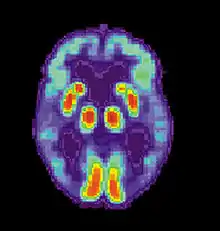

PET Normal brain

PET Alzheimer's disease

Successful remembering involves recognition that something is familiar and recall of the context in which it was previously experienced. With age, the ability to discriminate between new and previous events begins to fail, and errors in recalling experiences become more common.[35] Larry Jacoby of New York University (1999) demonstrated how common these errors can become, lending a better understanding to why recognition errors are particularly common in Alzheimer's disease. In Jacoby's study, participants were given two lists of words: one to read and one which they would hear read aloud. All subjects were then given a "test" list which contained some words they had read, some they had heard, and some novel words; the subjects had to determine which words were which.[35] Jacoby found that university students and 75-year-olds were equally likely to correctly recognize whether or not the word had been presented, but 75-year-olds were much more likely to mistake whether the word was spoken or read. In other words, while recognition of familiar versus novel words remained relatively stable across age groups, source confusion increased dramatically with age.

These studies show that simply rehearsing material may not always work to improve memory. In the Jacoby study, older adults who read a word several times were likely to accurately judge it as familiar but were then more likely to think they had heard the word read aloud, rather than reading it themselves.[35] Jacoby explains that— because repetition of a word caused recognition to go up but ability to correctly remember the source to go down— recognition and source monitoring are likely separate neurological processes.[35] This may shed some light on the common phenomenon of Alzheimer's patients mistaking frequently presented non-famous faces as being those of celebrities[37] or asking the same question repeatedly. Patients may recognize faces or identify that the subject of the question is important and was discussed recently, but they have no memory for the meaning attached to these common stimuli and so will misattribute this familiarity or simply ask again.[35]